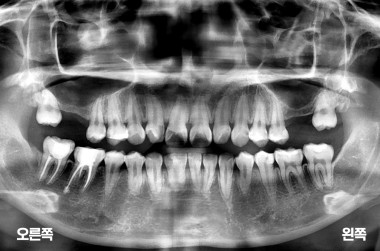

어금니 상악동거상술